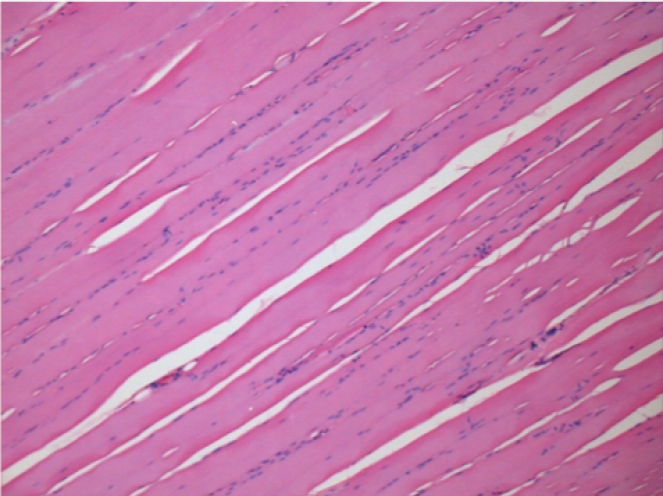

Histology

On Wistar rats

-hematoxilin-eosin

L:Pretibial-No treatment